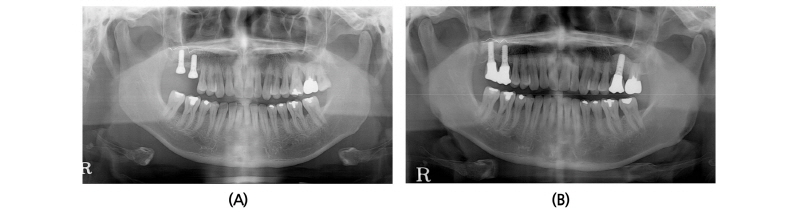

A 40-year old male patient who had missing tooth of first molar at right maxilla (#16) and discomfort of chewing in both posterior teeth visited the clinic for the periodontal treatment (Fig. 5A). Vertical tooth mobility was found on right maxillary second (#17), third molars (#18) and left maxillary first molar (#26) with severe bone loss. The patient was diagnosed as generalized chronic advanced periodontitis and #17, 18, 26 and 28 teeth were planned to be extracted. Nonsurgical periodontal treatment in whole mouth and periodontal surgeries at both mandibular posterior teeth were done. After 3 months of healing in the right maxillary edentulous area, sufficient buccopalatal width and vertical dimension about 12 mm from the soft tissue level was shown (Fig. 5B, 5C). Computed tomography revealed deficiency in the RBH with pneumatized sinus floor and horizontal bone loss especially in #17 site (Fig. 6A), which was measured to be 5 mm (Fig. 6B). The RBH of #16 sites was about 7 mm and spontaneous SFE with implant installation in both #16 and #17 using hybrid technique was planned. After flap reflection, a linear osteotomy at the lateral wall was prepared using piezoelectric device (Fig. 7A). Mesiodistal dimension of the opening was about 8 mm centered at the #17 site and slightly extended to the #16 site. The osteotomy positioned at 7~8 mm from the crest in #17 area and ran parallel along the sinus floor which had inclination from the #16 site. After detachment of the Schneiderian membrane limited in the floor, a serial drilling one step ahead of the final diameter was done with sinus elevator inserted through the lateral opening (Fig. 7B). MBCP® of 0.5 g was grafted via lateral osteotomy site and through the drilling site using osteotomes. Drilling of the final diameter was prepared and Straumann SLA® diameter 4.8 WN with 10 mm length implant was installed at both #16 and #17 (Fig. 7C). Absorbable collagen sponge (CollaTape®, Zimmer Dental, Carlsbad, CA) was covered on the lateral osteotomy site (Fig. 7D) and non-submerged healing was done (Fig. 7E). Dome-shaped sinus floor augmentation around the implant apex was shown immediately after the surgery (Fig. 8A) and prosthetic delivery was done within 3 months of healing periods. The level of SFE was maintained through 4-year of follow-up (Fig. 8B).